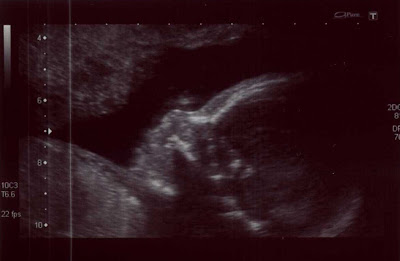

The sonographer took measurements of the baby's bones etc, but because he/she was lying face down, she couldn't get to the heart or face to check them. She ended up jabbing my belly a fair bit, but the baby didn't respond - lazy baby!

In the end I had to get up, jump up and down and shake my belly, poor thing. But it worked. When I lay back on the table the baby was wriggling around, head up. She looked at the heart and the face, and all looks well. The baby is measuring well for 21 weeks; no "whopper" baby for me! The baby even yawned a few minutes later; a result of all the poking I'm thinking... I realise that this might not be big news for you, but at the moment, everything the baby does is beyond amazing to me.

They're only supposed to give us three photos in total, and she gave us three identical photos of the profile, but accidentally slipped the others in my notes so I took them home. I think they're supposed to keep them for their files. Oops. I've taken advantage and scanned them all, and will let my midwife know I have them when I see her in January. But for now...

Baby's Profile: